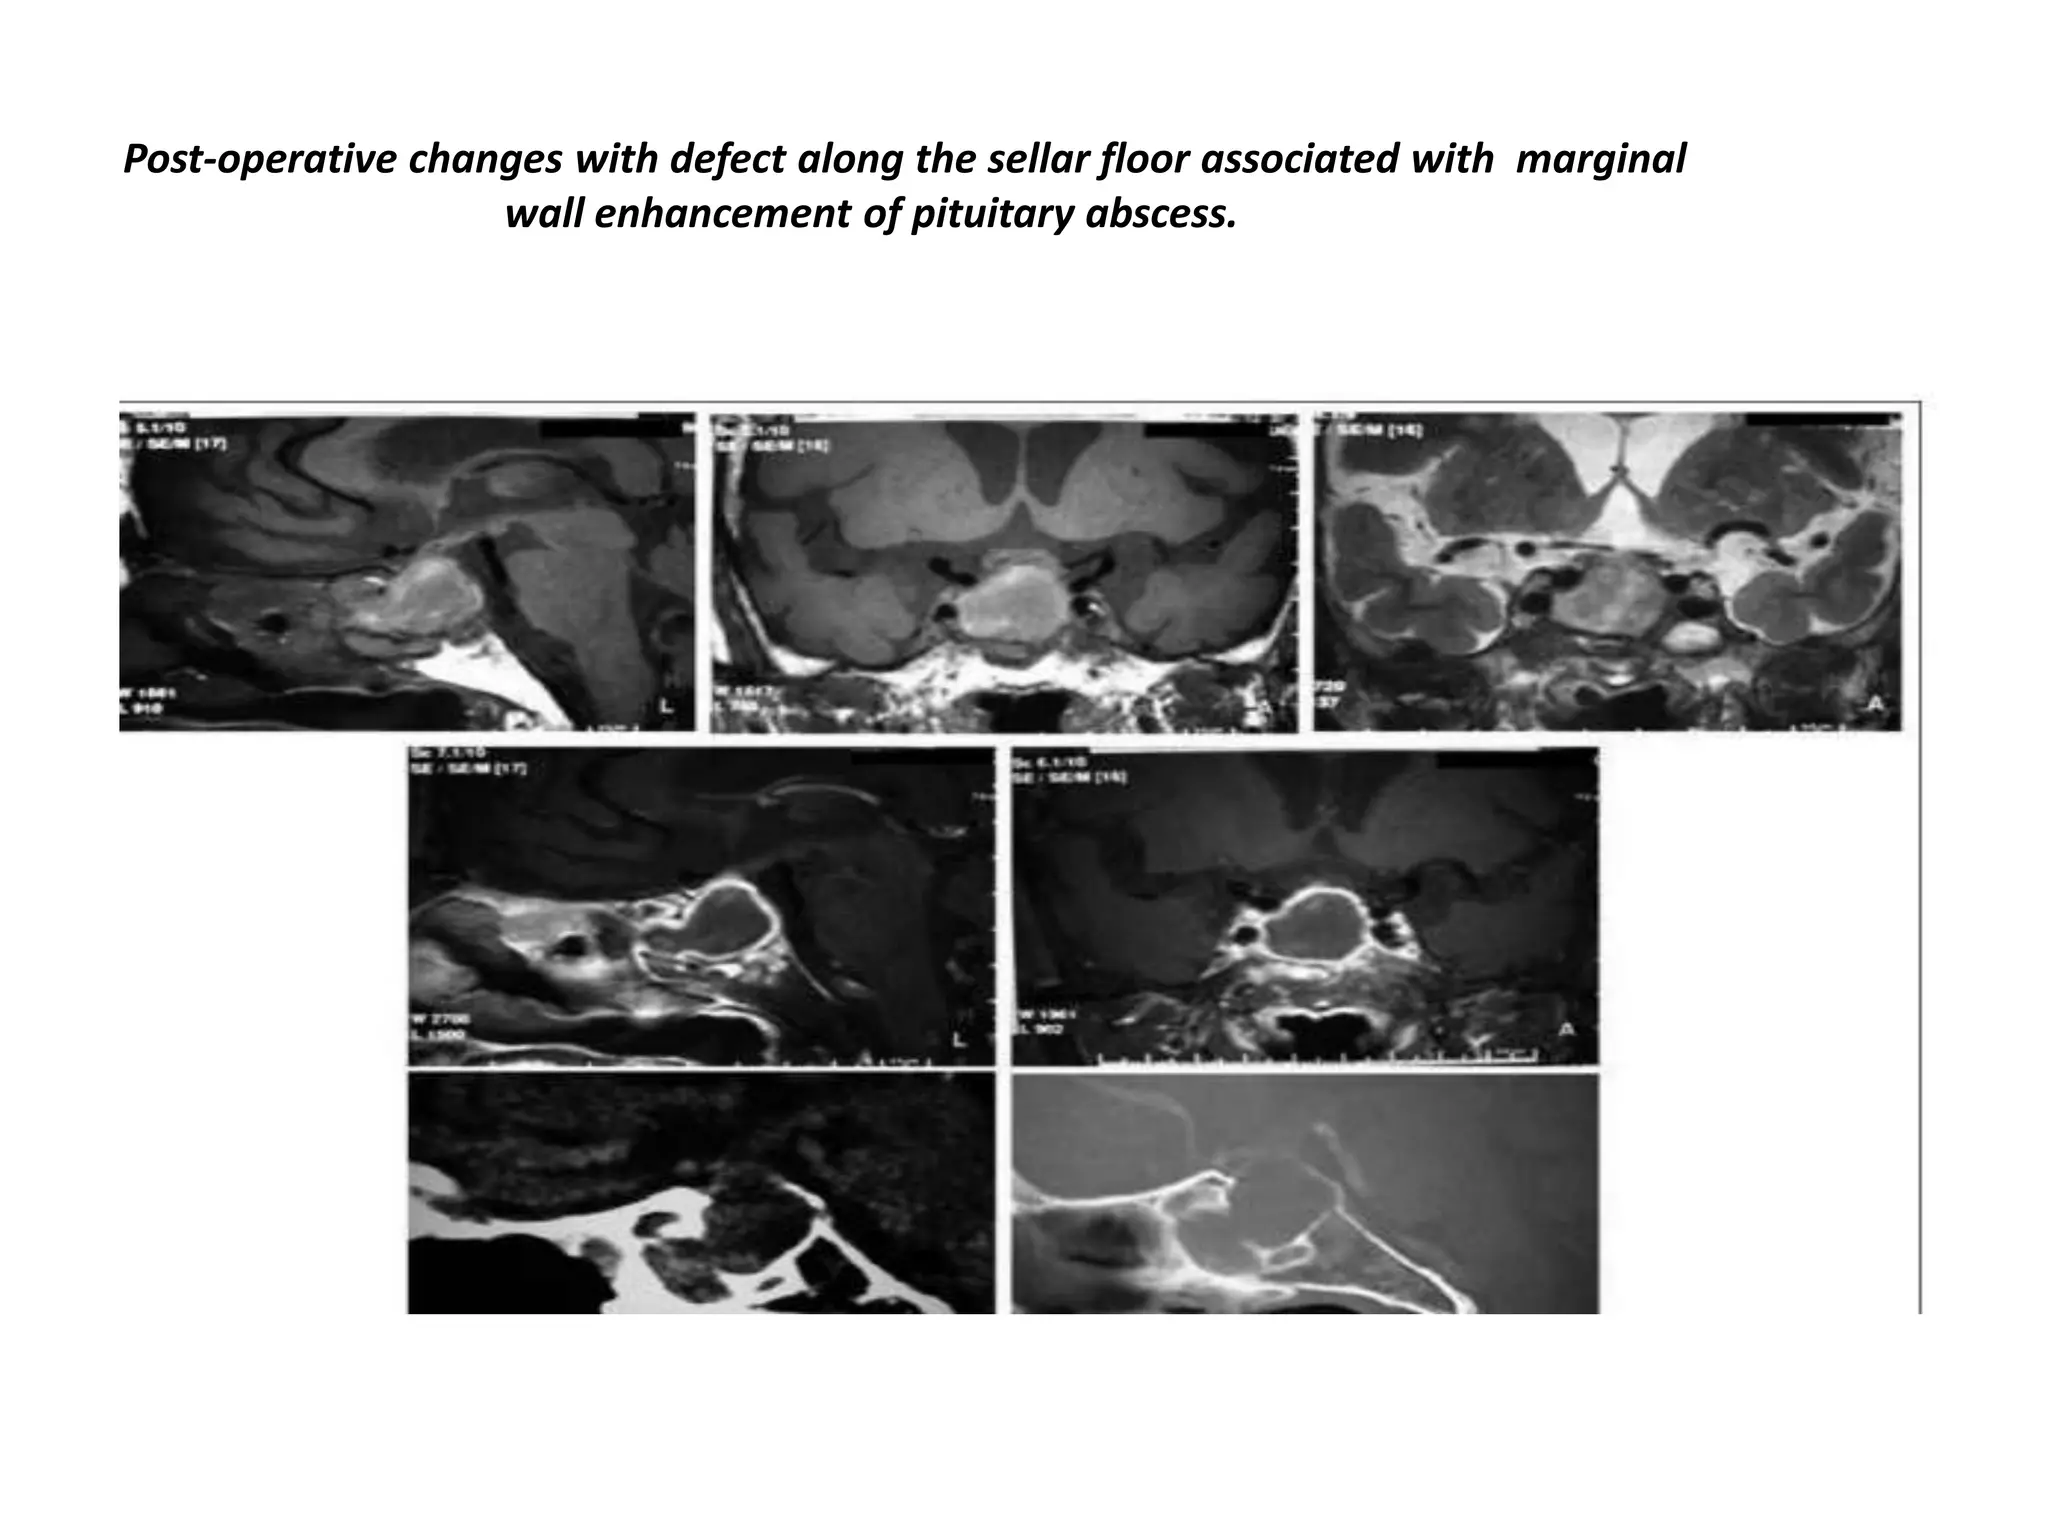

Post-operative changes with defect along the sellar floor associated with marginal

wall enhancement of pituitary abscess.

Post-operative changes withdefect along the sellar floor associated with marginal wall enhancement of pituitary abscess.